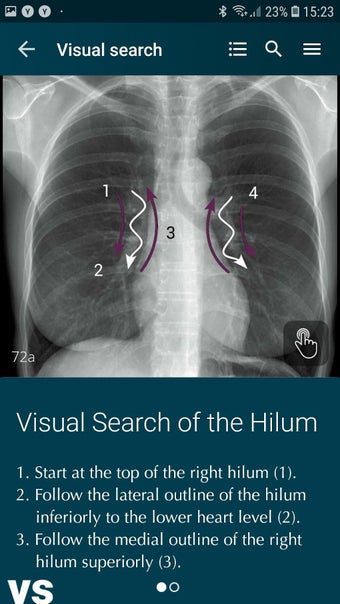

Radioloji'yi Keşfet: Göğüs Röntgeni Yorumlama, göğüs röntgeninin yorumlanmasının anlaşılmasını artırmak için tasarlanmış bir eğitim uygulamasıdır ve doktorlar, tıp öğrencileri ve radyologlar tarafından kullanılması amaçlanmaktadır. Uygulama, en küçük detayları görüntülemek için yakınlaştırılabilecek yüksek kaliteli görüntüler ve her bulgunun önemini anlamanıza yardımcı olacak bir sesli yorum içerir.

Ayrıca, uygulama bir hastanın göğüs röntgenini incelemeleri sırasında başvurabilecekleri bir dizi nasıl yapılır içerir. Uygulamadaki nasıl yapılır adımlarını takip ederek, kullanıcılar birçok farklı bulguyu doğru bir şekilde tanımlayabilecekler ve her birini bir hastalığın teşhisi için nasıl doğru bir şekilde kullanacaklarını öğrenebileceklerdir.